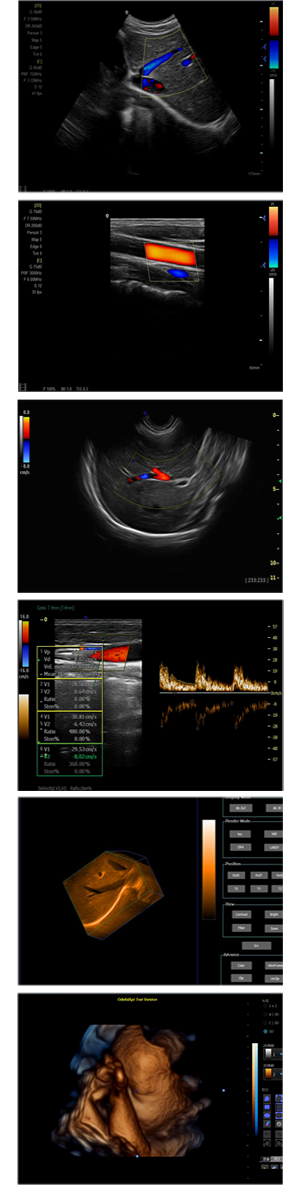

XF-7600型,秉承先鋒彩超技術之精華,擁有高雅大氣的獨特外型,為最新一代應用型數(shù)字彩色多普勒診斷系統(tǒng),魅力與實力相融合??蓮V泛適用于腹部、婦產(chǎn)科、心臟、小器官、乳腺、肌骨及外周血管等諸多方面的診查,讓您在臨床超聲診斷應用領域得心應手,綻放異彩!

突破的成像技術

● 3D/ 4D成像技術/選配

● 應用于腹部、腎臟、泌尿系統(tǒng)、產(chǎn)科、婦科、盆腔、大動脈、肌肉組織、小器官、乳腺、心臟等

● 能量多普勒成像(PDI)

● 彩色血流量圖(CDE)

● 脈沖頻譜多普勒成像(PW)

● 組織諧波成像技術